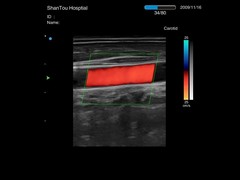

• Disponible opciones de Doppler Pulsado y Color Doppler

Opción de Mapeo de Flujo a Color (Color Flow Mapping) :